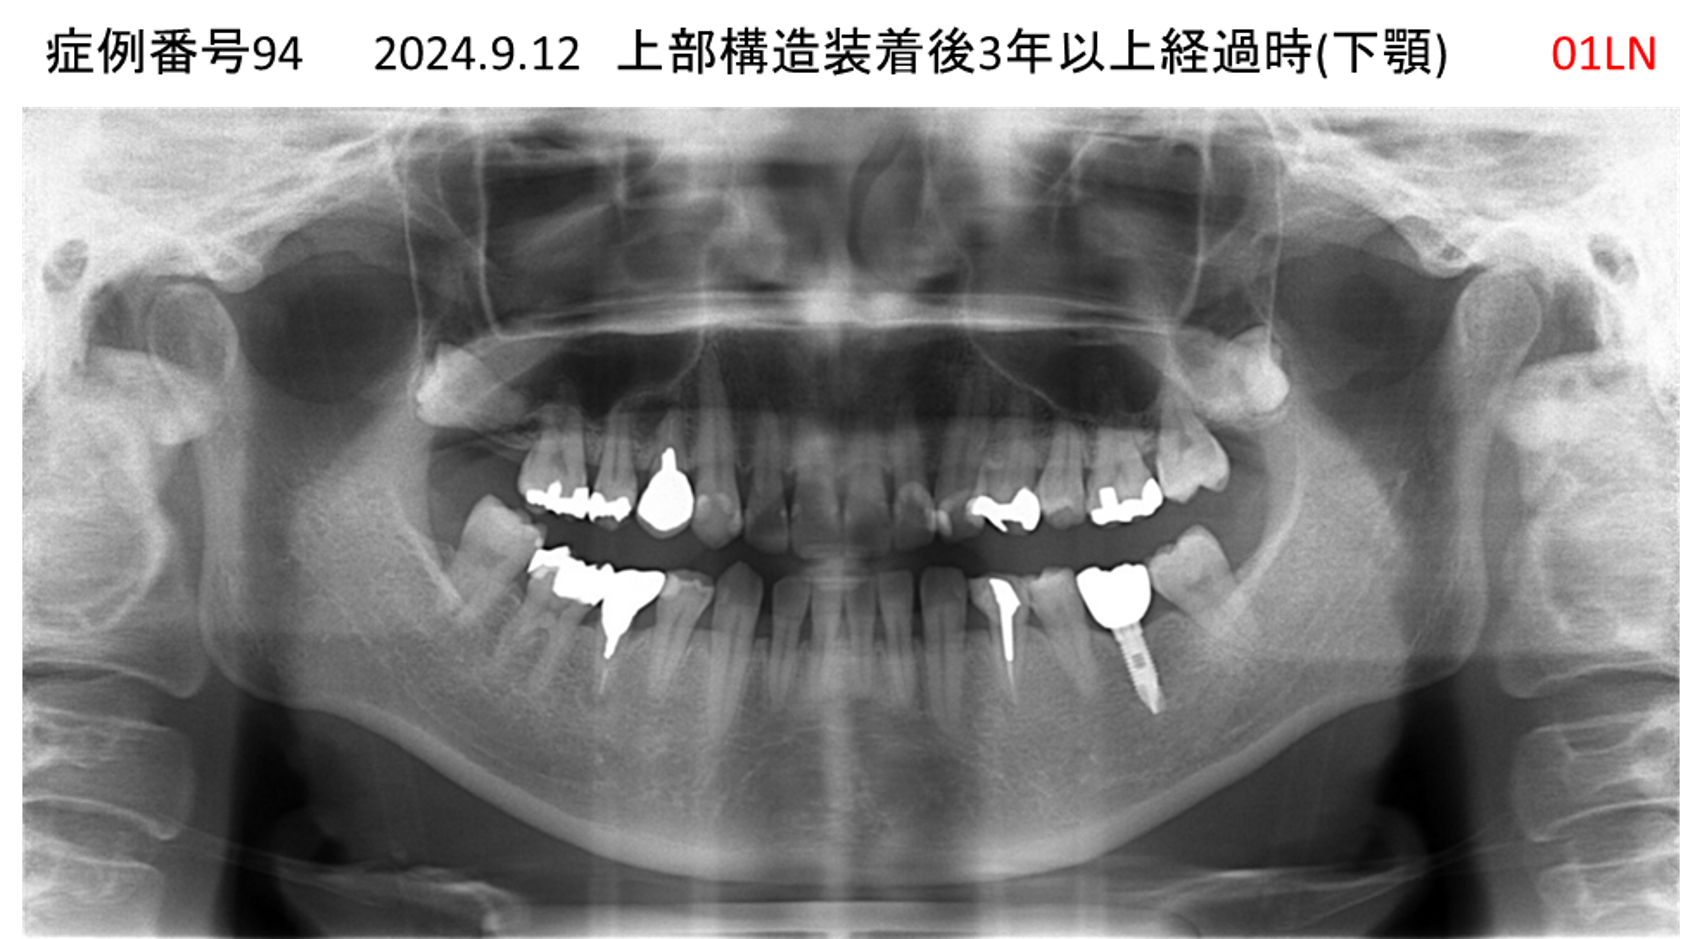

奥歯で噛めない患者様のインプラント症例

| 治療名称 |

インプラント |

| 治療費用 |

365万円+税 |

| 治療期間 |

5か月 |

| 患者さんの症状(主訴) |

奥歯で噛めない。上の前歯が揺れてきた。 |

| 治療内容 |

抜歯即時インプラント |

| 治療結果 |

食事に困らない。見た目がとても良くなった。 |

| 治療の注意点(リスク/副作用) |

インプラントが壊れたら再治療が必要 |